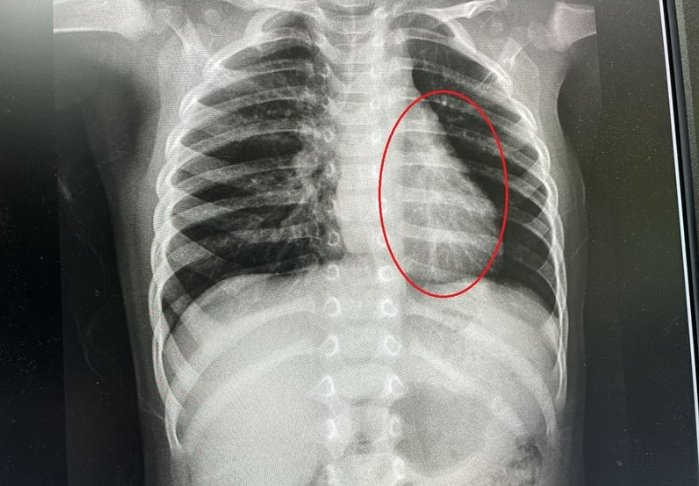

重度黴漿菌感染多久會好?時間可能長達四到六週或更久。當感染導致肺炎或其他器官損傷時,恢復期涉及抗生素療程和復健。例如,肺炎患者需住院治療,症狀緩解後仍可能有殘餘咳嗽數週。黴漿菌感染多久會好在這種情況較難預測,併發症如敗血症會延遲康復。黴漿菌感染多久會好必須配合醫師監測,避免慢性問題。研究顯示,未及時處理的重度感染,恢復期可倍增。

黴漿菌感染症狀併發症時?肺炎最常見,症狀包括呼吸急促、胸悶和發紺(皮膚發藍)。其他如腦膜炎(頭痛、頸僵)或心包炎(胸痛)。黴漿菌感染症狀的併發症需透過影像檢查確認。預防在於早期控制黴漿菌感染症狀。